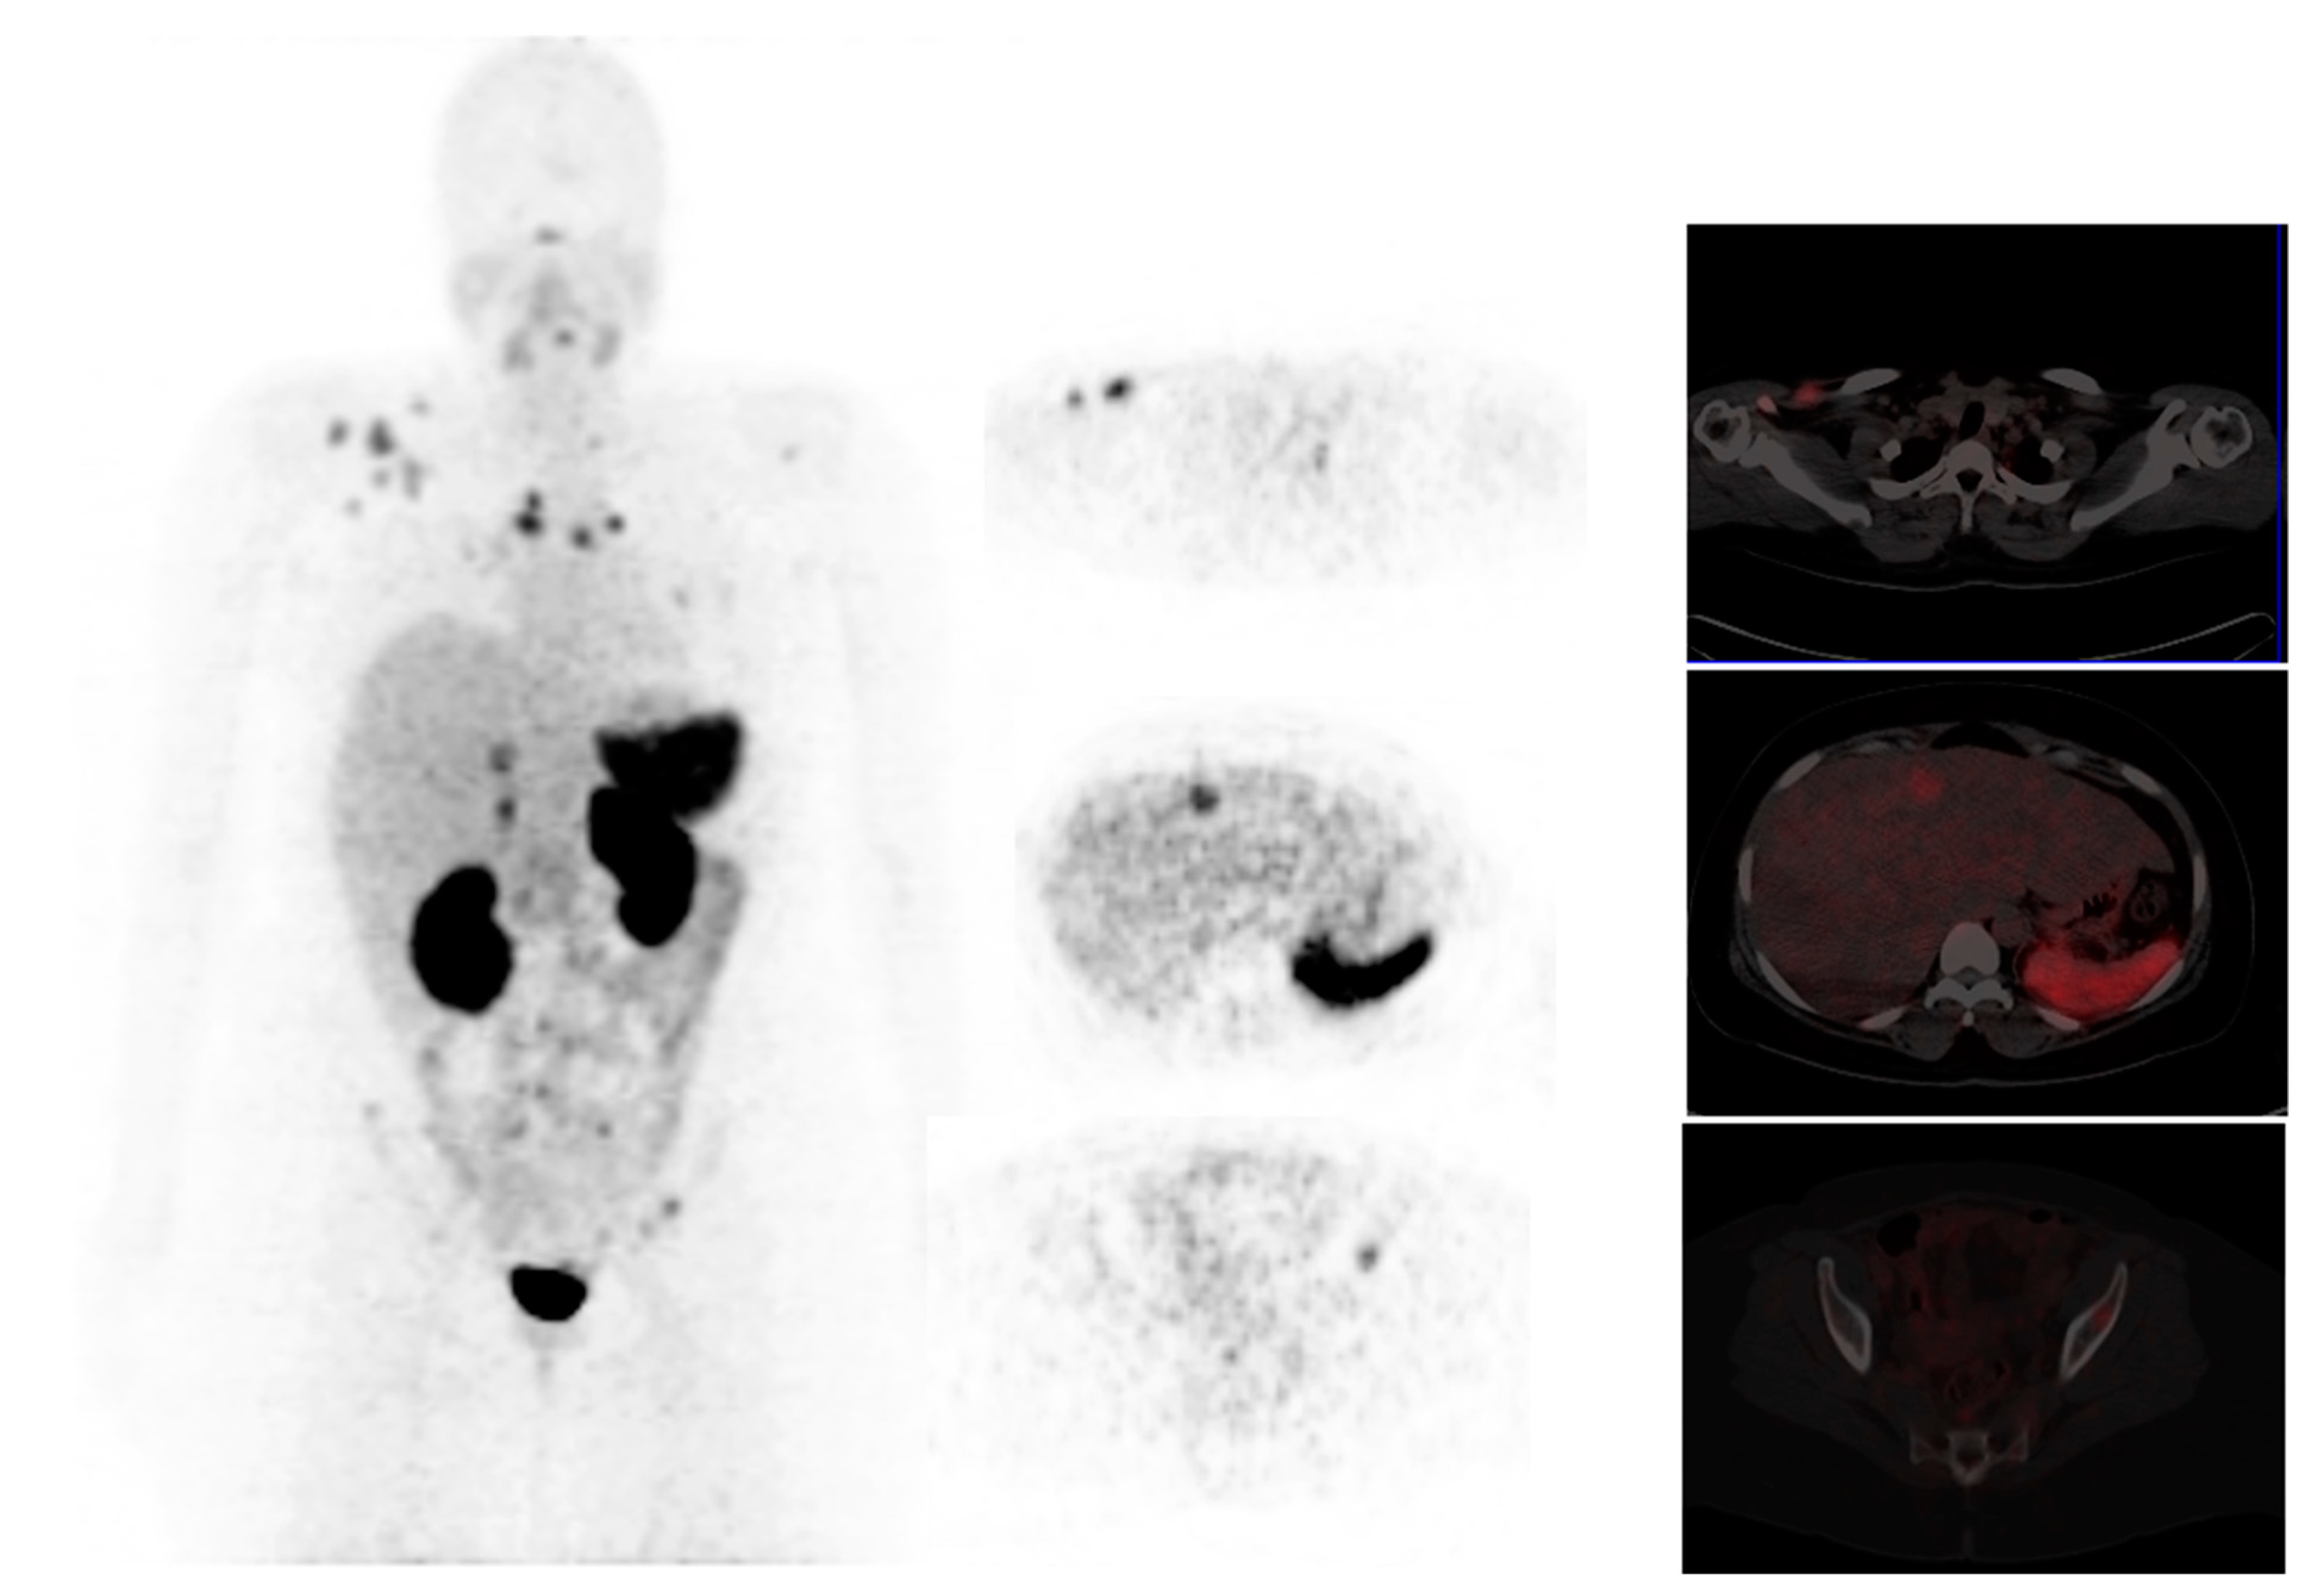

- Vag, T.; Steiger, K.; Rossmann, A.; Keller, U.; Noske, A.; Herhaus, P.; Ettl, J.; Niemeyer, M.; Wester, H.-J.; Schwaiger, M. PET imaging of chemokine receptor CXCR4 in patients with primary and recurrent breast carcinoma. EJNMMI Res. 2018, 8, 90. [Google Scholar] [CrossRef]